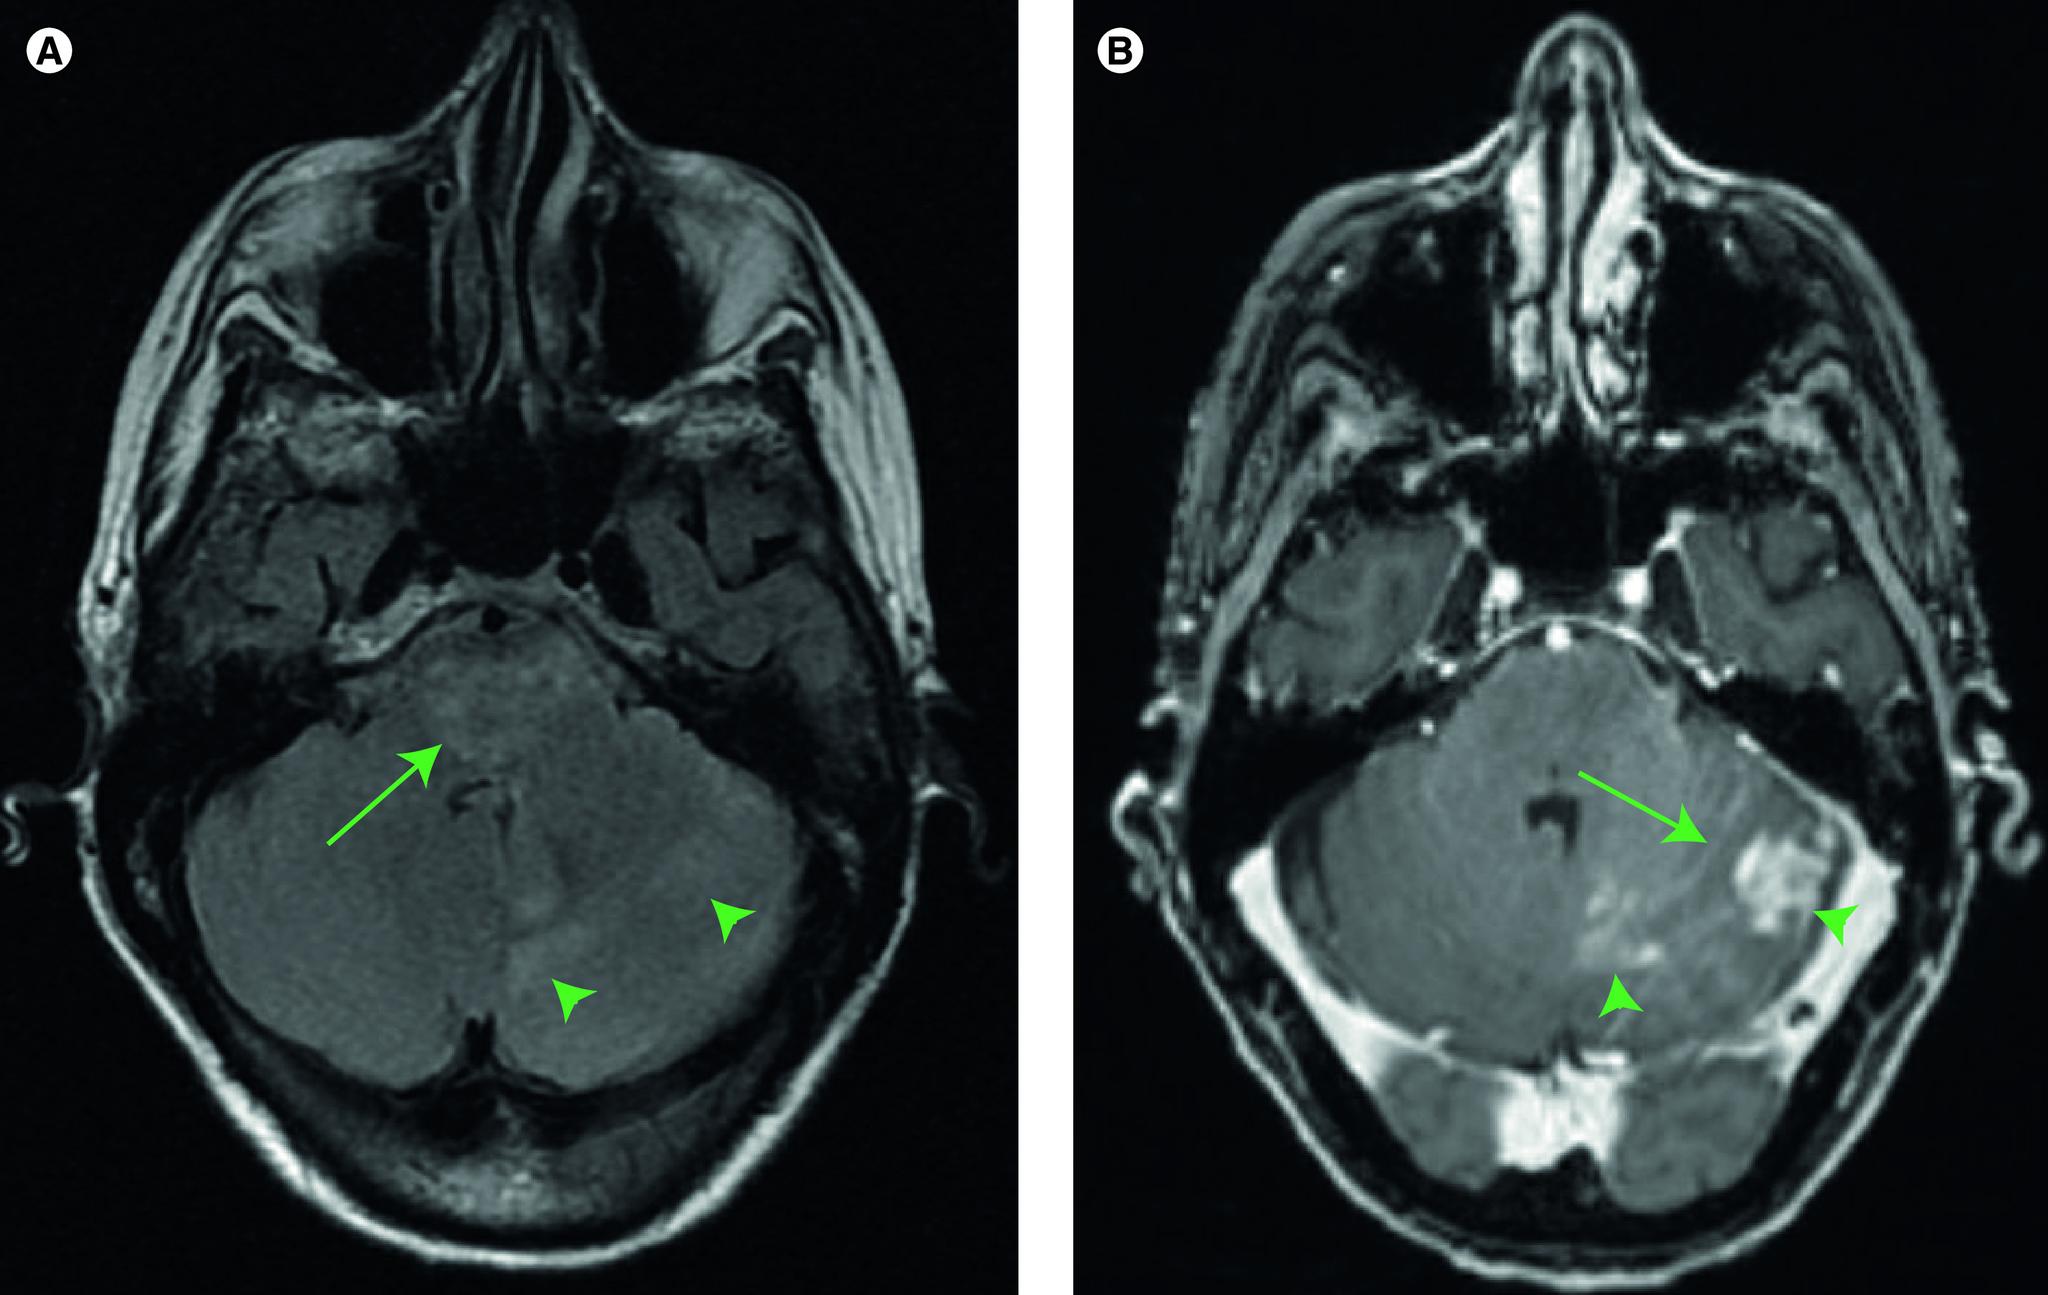

一名 83 岁女性患有弥漫性中线胶质瘤,伴有 H3 K27M 突变。

Diffuse midline glioma with H3 K27M-mutation in an 83-year-old woman.

Diffuse midline gliomas harboring histone H3 K27M mutations are most commonly found in the brainstem of children. This mutation confers a WHO grade IV designation and is associated with a particularly poor prognosis. Although traditionally considered to be a disease of children and young adults, a number of recent reports have described H3 K27M mutations in older adults with diffuse midline gliomas. Here, we present the unusual case of a diffuse midline glioma in the pons and cerebellum of an 83-year-old woman and review the evolving clinical literature on this entity in adults. This case underscores that it may occur even in older adults, in whom prognostic and treatment paradigms used in pediatrics may not be directly applicable.

摘要

弥漫性中线胶质瘤中存在组蛋白 H3 K27M 突变,最常见于儿童的脑干中。这种突变赋予了世界卫生组织(WHO)分级 IV ,并且与预后特别差相关。尽管传统上认为这是一种儿童和青年期的疾病,但最近有一些报告描述了在患有弥漫性中线胶质瘤的老年患者中存在 H3 K27M 突变。在这里,我们报告了一例罕见的 83 岁女性桥脑和小脑弥漫性中线胶质瘤,并回顾了关于成人这一实体的不断发展的临床文献。这个病例强调了它甚至可能发生在老年患者中,在这些患者中,儿科中使用的预后和治疗模式可能并不直接适用。